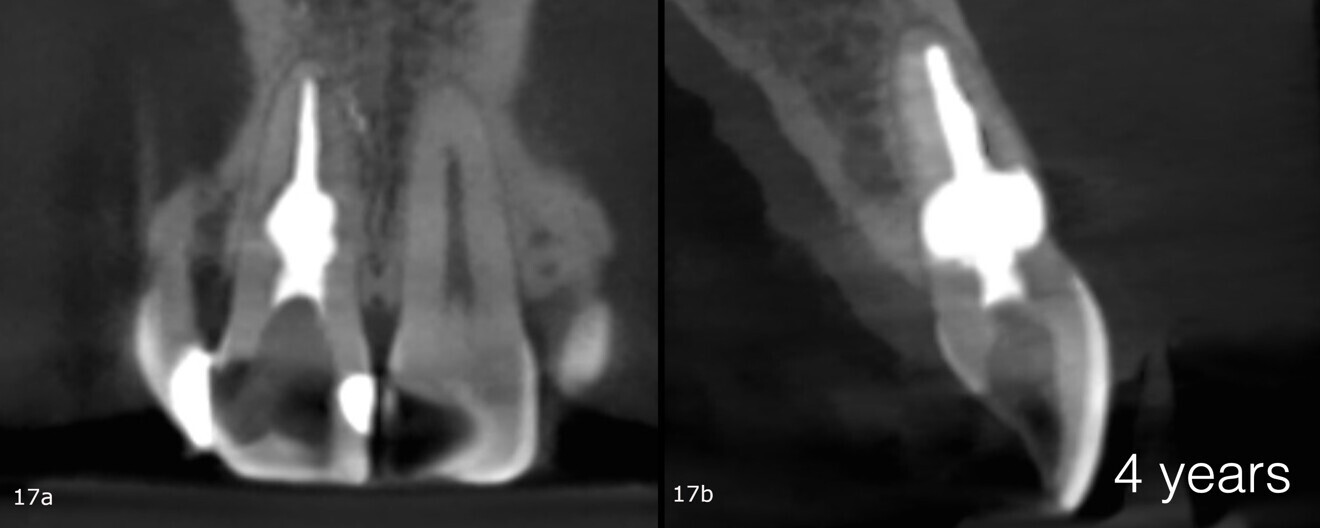

Recall appointments was performed after two (Figs. 16a & b) and four years (Figs. 17a & b). The radiographic examination showed the presence of bundle bone. The periodontal status was stable, and the tooth remained asymptomatic.

Figs. 17a & b: CBCT scan taken four years after the treatment.